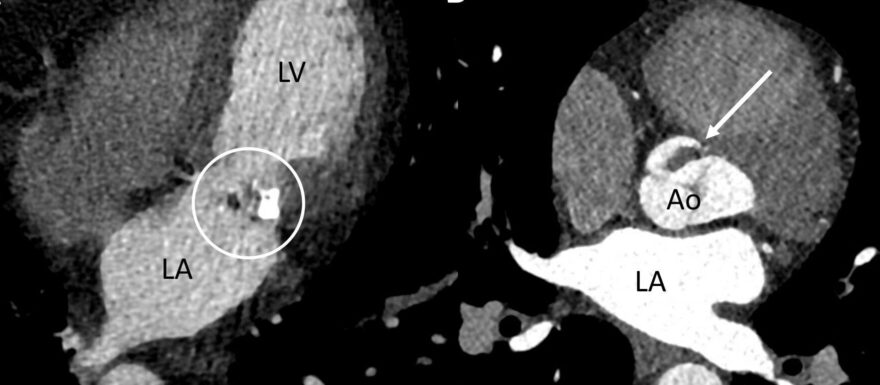

Patiënten met een herseninfarct door een cardiale emboliebron hebben vaker ernstigere symptomen, een hogere kans op een recidief herseninfarct en een slechtere functionele uitkomst dan patiënten met een herseninfarct door een andere oorzaak. Deze patiëntengroep heeft doorgaans een indicatie voor anticoagulantia in plaats van trombocytenaggregatieremmers. De huidige diagnostiek naar een cardiale emboliebron in Nederland bestaat uit een ECG, ritmemonitoring en cardiale beeldvorming middels transthoracale echocardiografie. In de praktijk wordt de echo regelmatig niet, of pas dagen tot weken na het herseninfarct verricht met een groot risico op een diagnostisch delay. Een CT-scan van het hart als onderdeel van het acute scanprotocol is een modaliteit die kan leiden tot snellere en betere detectie van een cardiale emboliebron. Wereldwijd groeit het aantal ziekenhuizen dat CT-hart implementeert in hun acute scanprotocol. Met de toenemende ervaring kan de waarde van de CT-hart steeds beter ingeschat worden en lijkt het een veelbelovende modaliteit voor het optimaliseren van de beroertezorg. Er moeten echter nog stappen worden ondernomen om de waarde te evalueren in het kader van value-based healthcare, zoals het minimaliseren van scantijden en het scholen van zorgpersoneel.